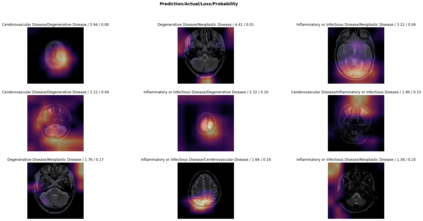

Magnetic Resonance Imaging (MRI) is a principal diagnostic approach used in the field of radiology to create images of the anatomical and physiological structure of patients. MRI is the prevalent medical imaging practice to find abnormalities in soft tissues. Traditionally they are analyzed by a radiologist to detect abnormalities in soft tissues, especially the brain. The process of interpreting a massive volume of patient's MRI is laborious. Hence, the use of Machine Learning methodologies can aid in detecting abnormalities in soft tissues with considerable accuracy. In this research, we have curated a novel dataset and developed a framework that uses Deep Transfer Learning to perform a multi-classification of tumors in the brain MRI images. In this paper, we adopted the Deep Residual Convolutional Neural Network (ResNet50) architecture for the experiments along with discriminative learning techniques to train the model. Using the novel dataset and two publicly available MRI brain datasets, this proposed approach attained a classification accuracy of 86.40% on the curated dataset, 93.80% on the Harvard Whole Brain Atlas dataset, and 97.05% accuracy on the School of Biomedical Engineering dataset. Results of our experiments significantly demonstrate our proposed framework for transfer learning is a potential and effective method for brain tumor multi-classification tasks.